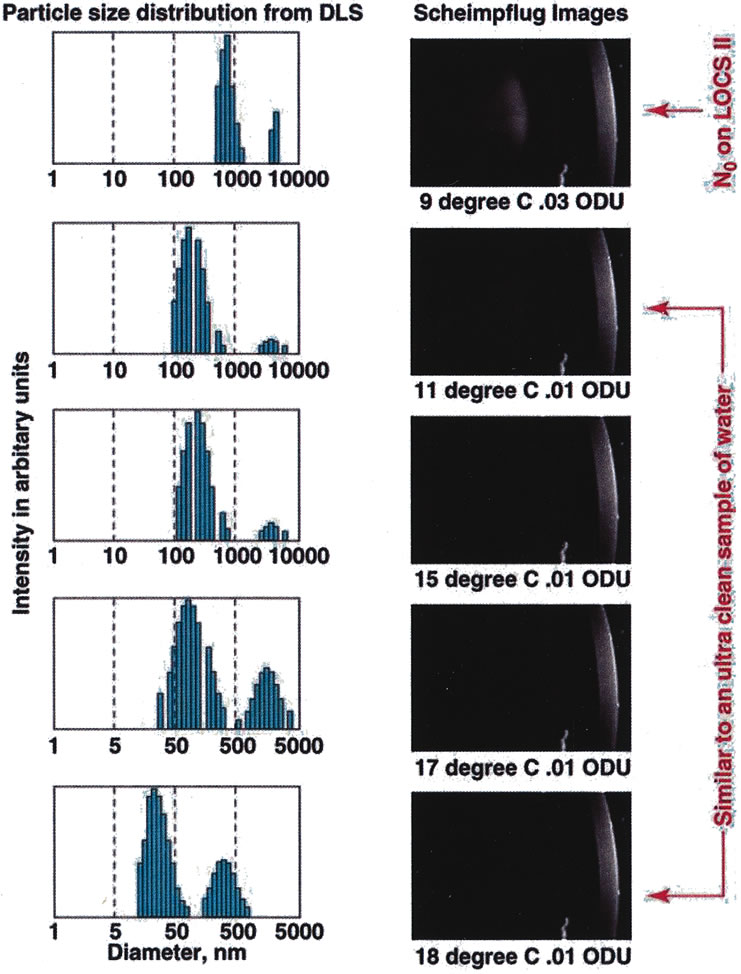

as the lens) can then be plotted (Figs. 10 and 11).  Fig. 10. Data obtained from a cold-induced cataract study using calf eyes. Data

on the left show the size distribution of lens proteins as the

cold cataract appears (as the temperature of the calf lens is lowered) showing

the shift from small to large molecular weight proteins (data

obtained from the dynamic light scattering [DLS] device) versus

Scheimpflug slit-lamp images of the same

calf lens as the temperature is correspondingly lowered and the cold

cataract appears. The DLS device picks up a shift in protein size much

earlier than the Scheimpflug camera shows the appearance of the cataract.66 Fig. 10. Data obtained from a cold-induced cataract study using calf eyes. Data

on the left show the size distribution of lens proteins as the

cold cataract appears (as the temperature of the calf lens is lowered) showing

the shift from small to large molecular weight proteins (data

obtained from the dynamic light scattering [DLS] device) versus

Scheimpflug slit-lamp images of the same

calf lens as the temperature is correspondingly lowered and the cold

cataract appears. The DLS device picks up a shift in protein size much

earlier than the Scheimpflug camera shows the appearance of the cataract.66

Clinically, DLS can be used to study cataracts noninvasively at the molecular

because of the very low laser power (50–100 μW) and short data acquisition time (5 seconds). In a cold-induced

cataract model experiment in which the cataract was simultaneously

monitored with both the DLS device and Scheimpflug camera (Fig. 10), the DLS picked up subtle changes in the lens quicker (2–3 orders

of magnitude earlier) than the Scheimpflug camera.66 The DLS measures the Brownian motion of the crystallins inside the lens. The